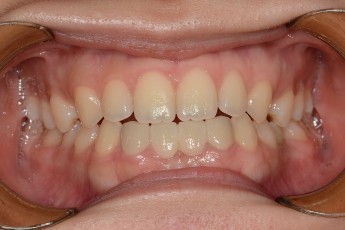

BEFORE & AFTER

- 돌출입교정